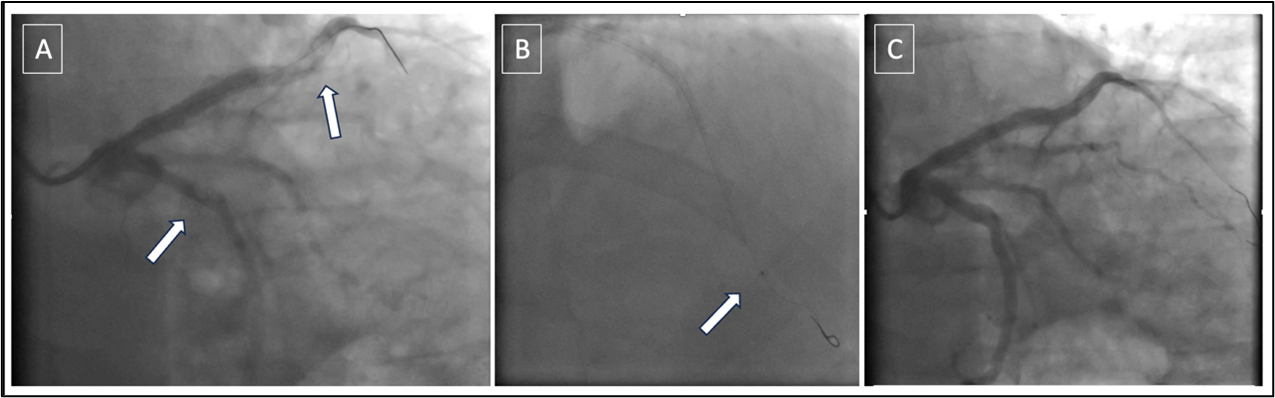

During the procedure, an inadvertent air entry into the left coronary arterial system occurred (Figure A; Video 1), and the patient promptly experienced chest pain and electrocardiographic changes.

Recognizing the critical nature of the situation, a 6-French thrombectomy catheter (Export Advance; Medtronic), typically used for thrombus aspiration, was employed proximal to the air bubble (Figure B). Using a controlled suction technique, the catheter successfully drew the air embolus into its lumen (Video 2), immediately restoring Thrombolysis in Myocardial Infarction (TIMI) 3 blood flow (Figure C; Video 3).